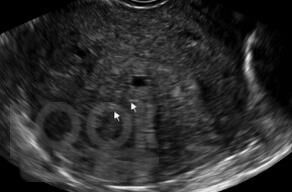

В учебном пособии на современном уровне освещены вопросы диагностики эндометриоза различной локализации. Предназначено для врачей акушеров-гинекологов с целью формирования научно-обоснованного подхода в диагностике эндометриоза и его локализаций с целью обнаружения заболевания на ранних стадиях и сохранения репродуктивного здоровья женщины.